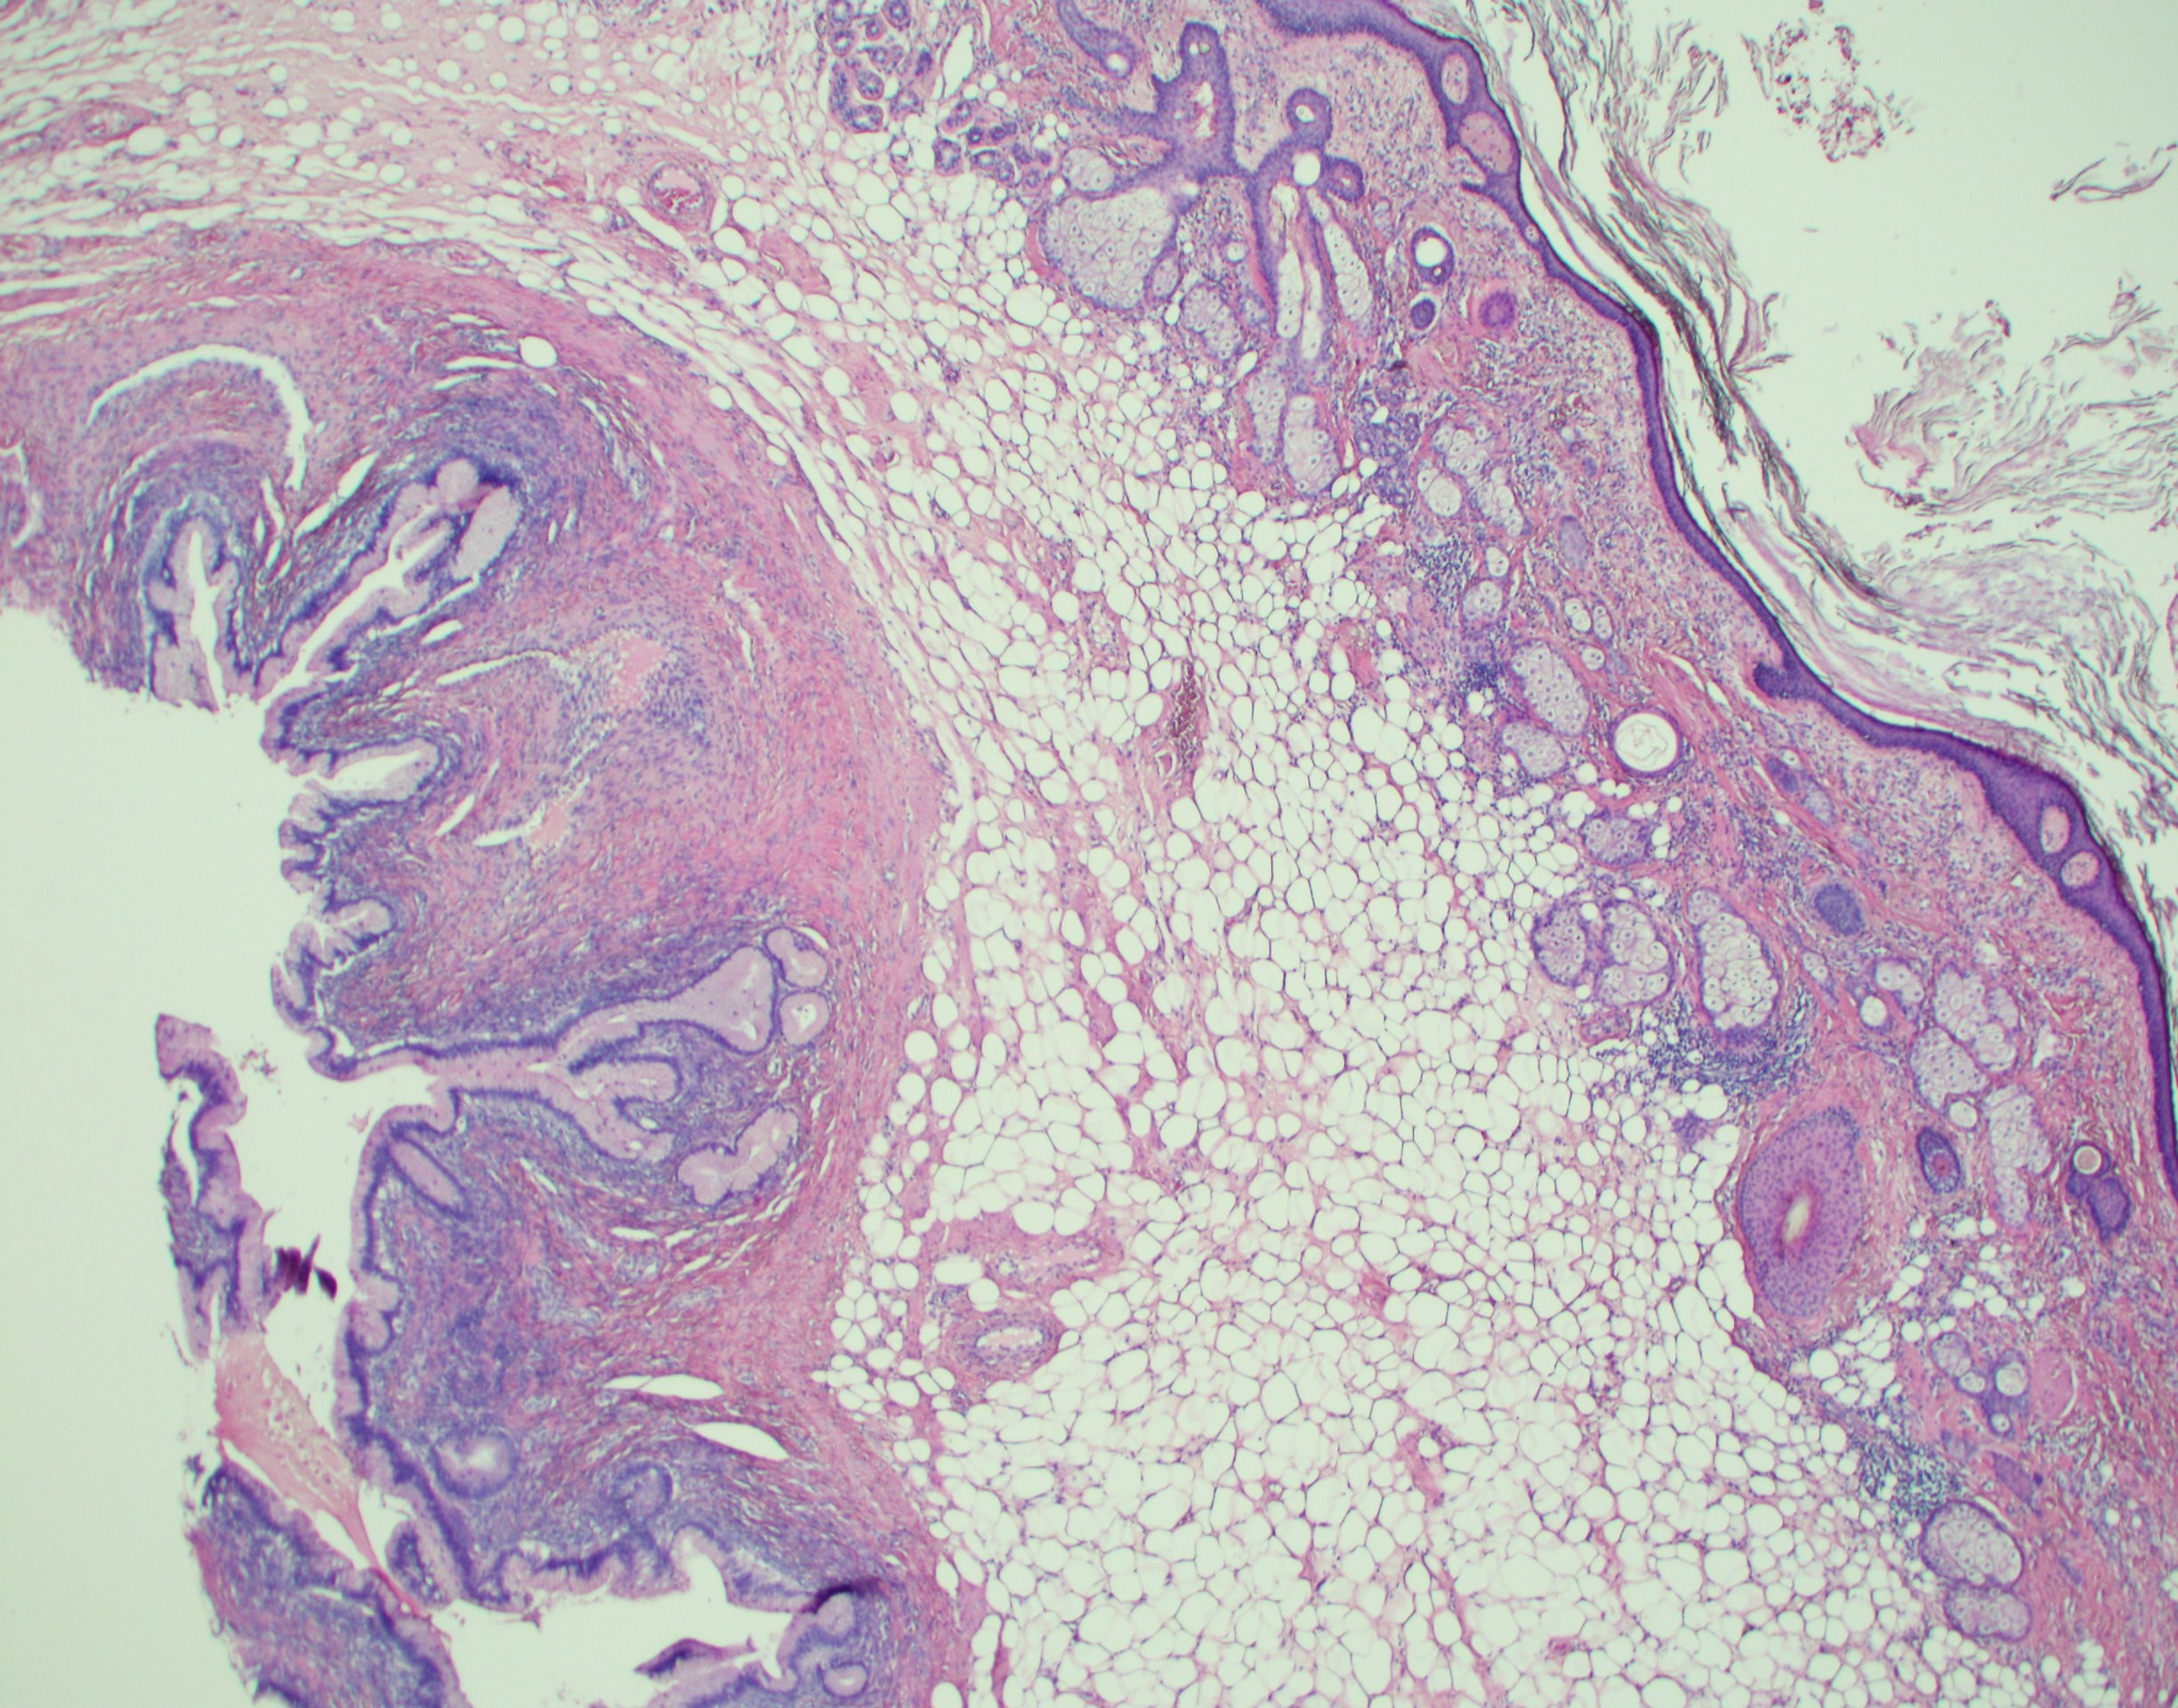

奇形腫は、毛髪、歯、筋肉、骨など、完全に発達した組織や器官を含む珍しいタイプの腫瘍です。奇形腫は尾骨、卵巣、睾丸で最も一般的ですが、体の他の場所で発生する可能性もあります。

奇形腫は一般に、成熟または未熟のいずれかとして説明されます。

- 成熟奇形腫は通常良性です (癌性ではありません)。しかし、外科的に除去した後に再び成長する可能性があります。

- 未熟奇形腫は悪性がんに発展する可能性が高くなります。

成熟奇形腫はさらに次のように分類されます。

- 嚢胞性: 液体を含む独自の嚢に囲まれています。

- 固体: 組織で構成されていますが、自己密閉されていません。

- 混合: 固体部分と嚢胞性部分の両方を含む

成熟嚢胞性奇形腫は、皮様嚢胞とも呼ばれます。

ほとんどの卵巣奇形腫は成熟型です。成熟卵巣奇形腫は、皮様嚢胞としても知られています。